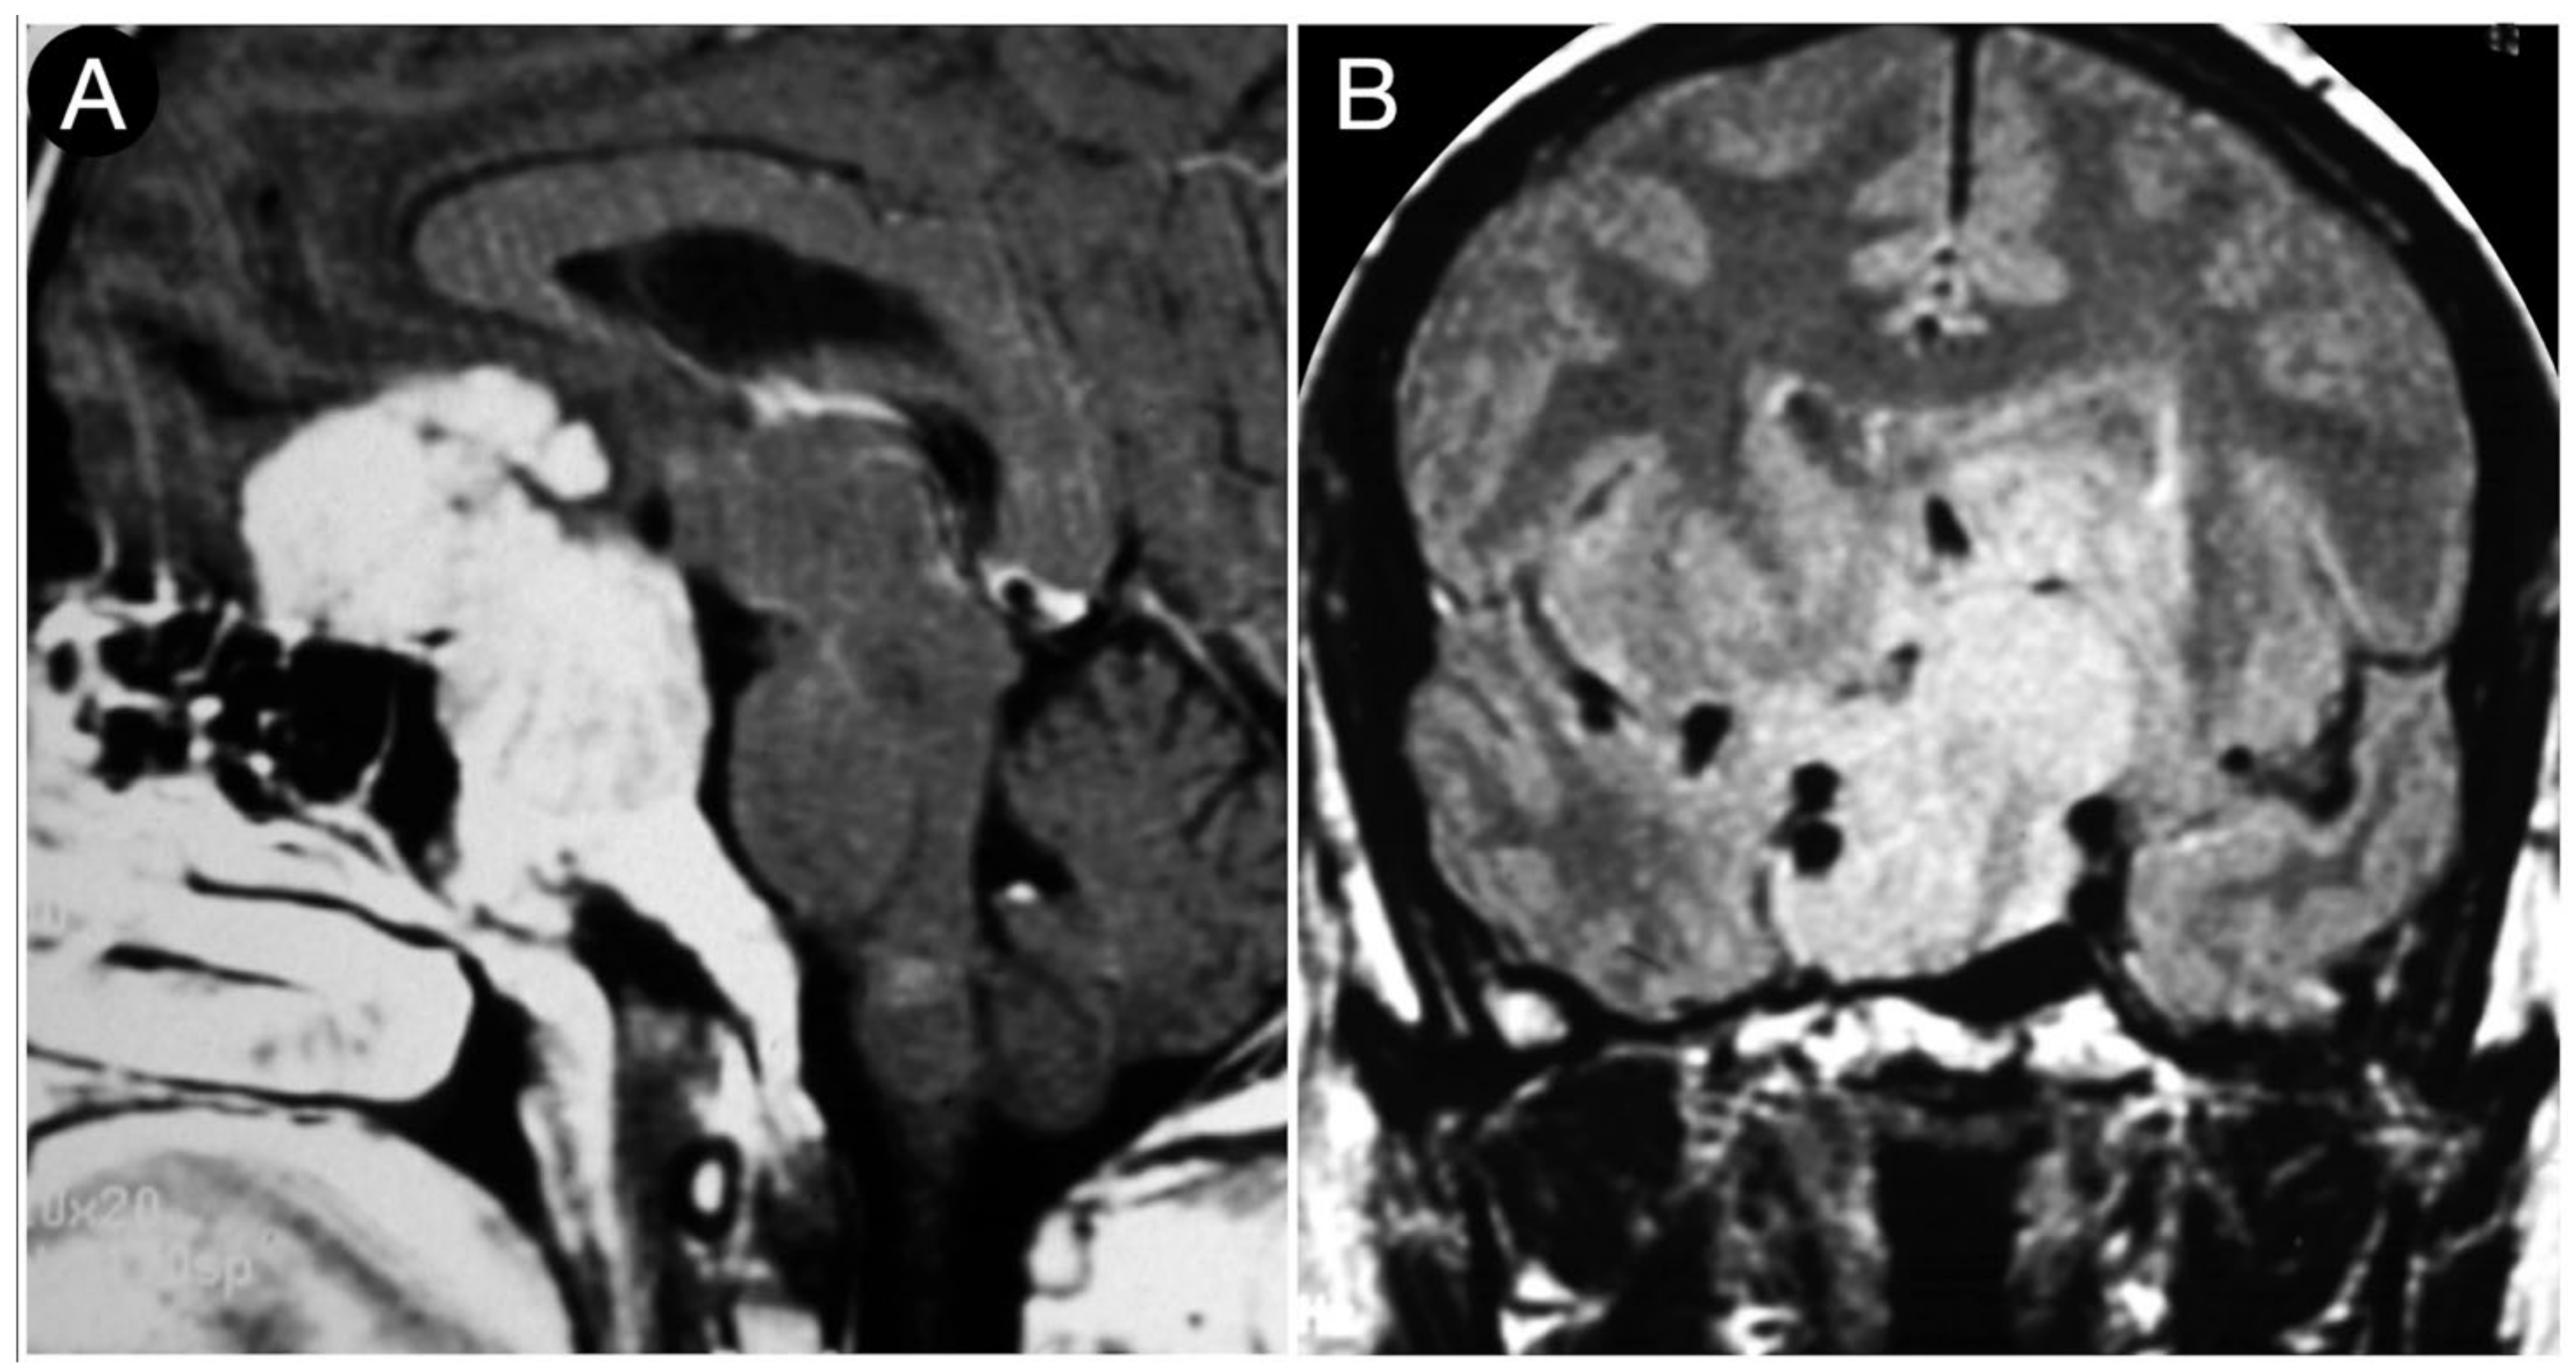

3.4. Retrosellar Extension

Case #7: Encasement of the Paraclinoid and Supraclinoid Internal Carotid Artery

3.5. Arterial Encasement